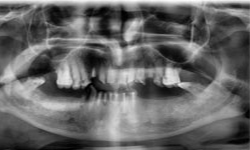

(10) Dental Implant - Full Mouth

Before Treatment

After Treatment

Patient came with a problem in chewing food and multiple loose teeth in upper and lower jaw and was interested in getting a whole new set of teeth in both the jaws. So after removal of all the weakened teeth and placement of multiple implants, he was given implant supported bridge.